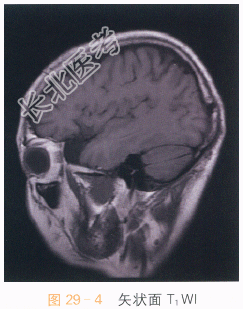

影像学资料如图29-1~图29-4所示。

读片分析:头颅横断面T₁WI、T₂WI见左侧中颅窝异常信号灶,呈长T₁WI、长T₂WI信号,边界清晰,左侧颞极受压,信号无明显异常改变;冠状面T₂WI及矢状面T₁WI亦可见左侧中颅窝长T₁WI、长T₂WI信号影,左侧颞极受压改变。结合患者病史,诊断为蛛网膜囊肿。